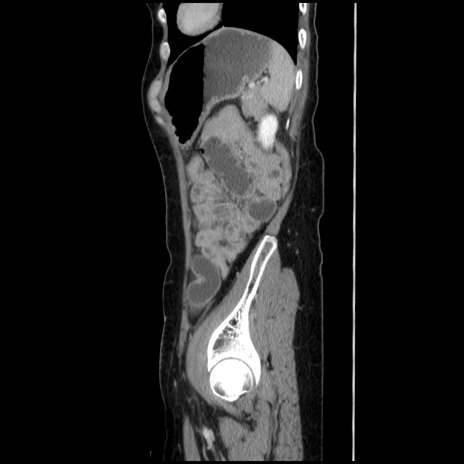

症例32(矢状断像)

横断像